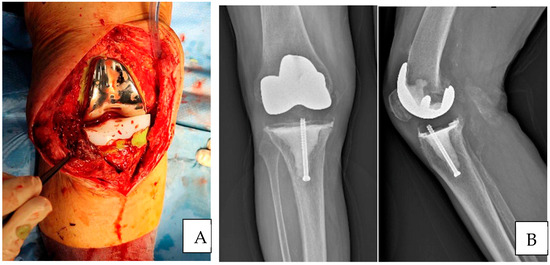

Surgical Technique